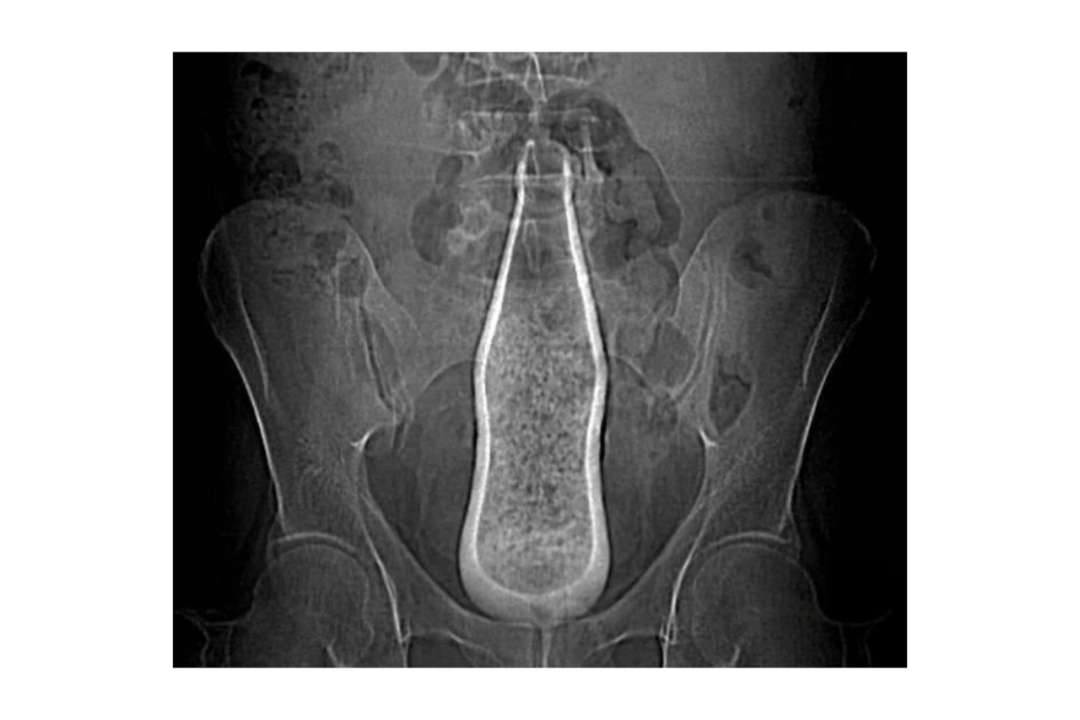

【#深圳14岁男孩网购假阳具塞入肛门#!“不小心整个滑进去”,医生提醒】#14岁男孩因好奇往肛门塞假阳具##肛门就像哆啦A梦的百宝袋#近日,深圳市松岗人民医院分享了一个案例:一名14岁的男孩因好奇心网购假阳具,并塞入了肛门,后来不小心整个滑了进去,肚子变得涨涨的,吃不下东西,也拉不出来。因就医及时,发生当晚就取出了,所以肛门、肠道未受到伤害。

对此,医生提醒:肛门内塞异物很难自然排出,多数需医生取出。长时间不取可能导致肠穿孔、肠梗阻等严重后果,越晚就医风险越大。同时医生建议家长:不要责怪孩子,否则下次遇到问题可能不敢求助;与其让孩子偷偷试错,不如大方引导;此外可带孩子接种HPV疫苗。(来源:综合深圳市松岗人民医院)